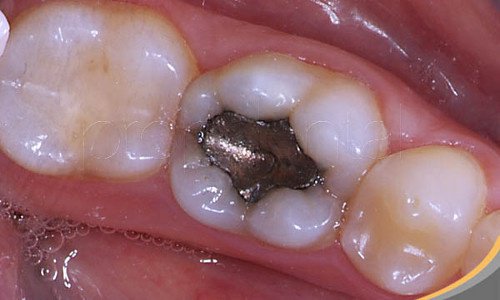

What are amalgam fillings?

Amalgam is a silver-colored material made up of a combination of various metals, particularly mercury, which dentists use to fill cavities that appear as the result of tooth decay.

Today most countries use other materials for dental fillings because numerous studies have shown that the levels of mercury are toxic both for the recipient of the filling, as well as the dentist who works with it.